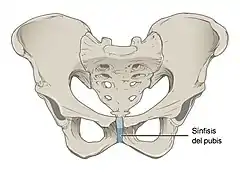

Fisiológicamente, el cuerpo humano tiene diversos tipos de articulaciones, como la sinartrosis (no móvil), anfiartrosis (con movimiento muy limitado -por ejemplo, la columna vertebral-) y diartrosis (mayor amplitud o complejidad de movimiento).

| Sinartrosis | Nula movilidad | Huesos del cráneo | |

Este tipo de articulaciones se mantienen unidas por un cartílago elástico y presentan muy poca movilidad. Un ejemplo de anfiartrosis son las articulaciones entre los cuerpos vertebrales en la columna vertebral. La sínfisis es un subtipo de articulación cuyas características son intermedias entre las diartrosis y las sinartrosis debido a que pueden presentar una cavidad articular dentro del ligamento interóseo, como la sínfisis del pubis y articulación sacroilíaca.